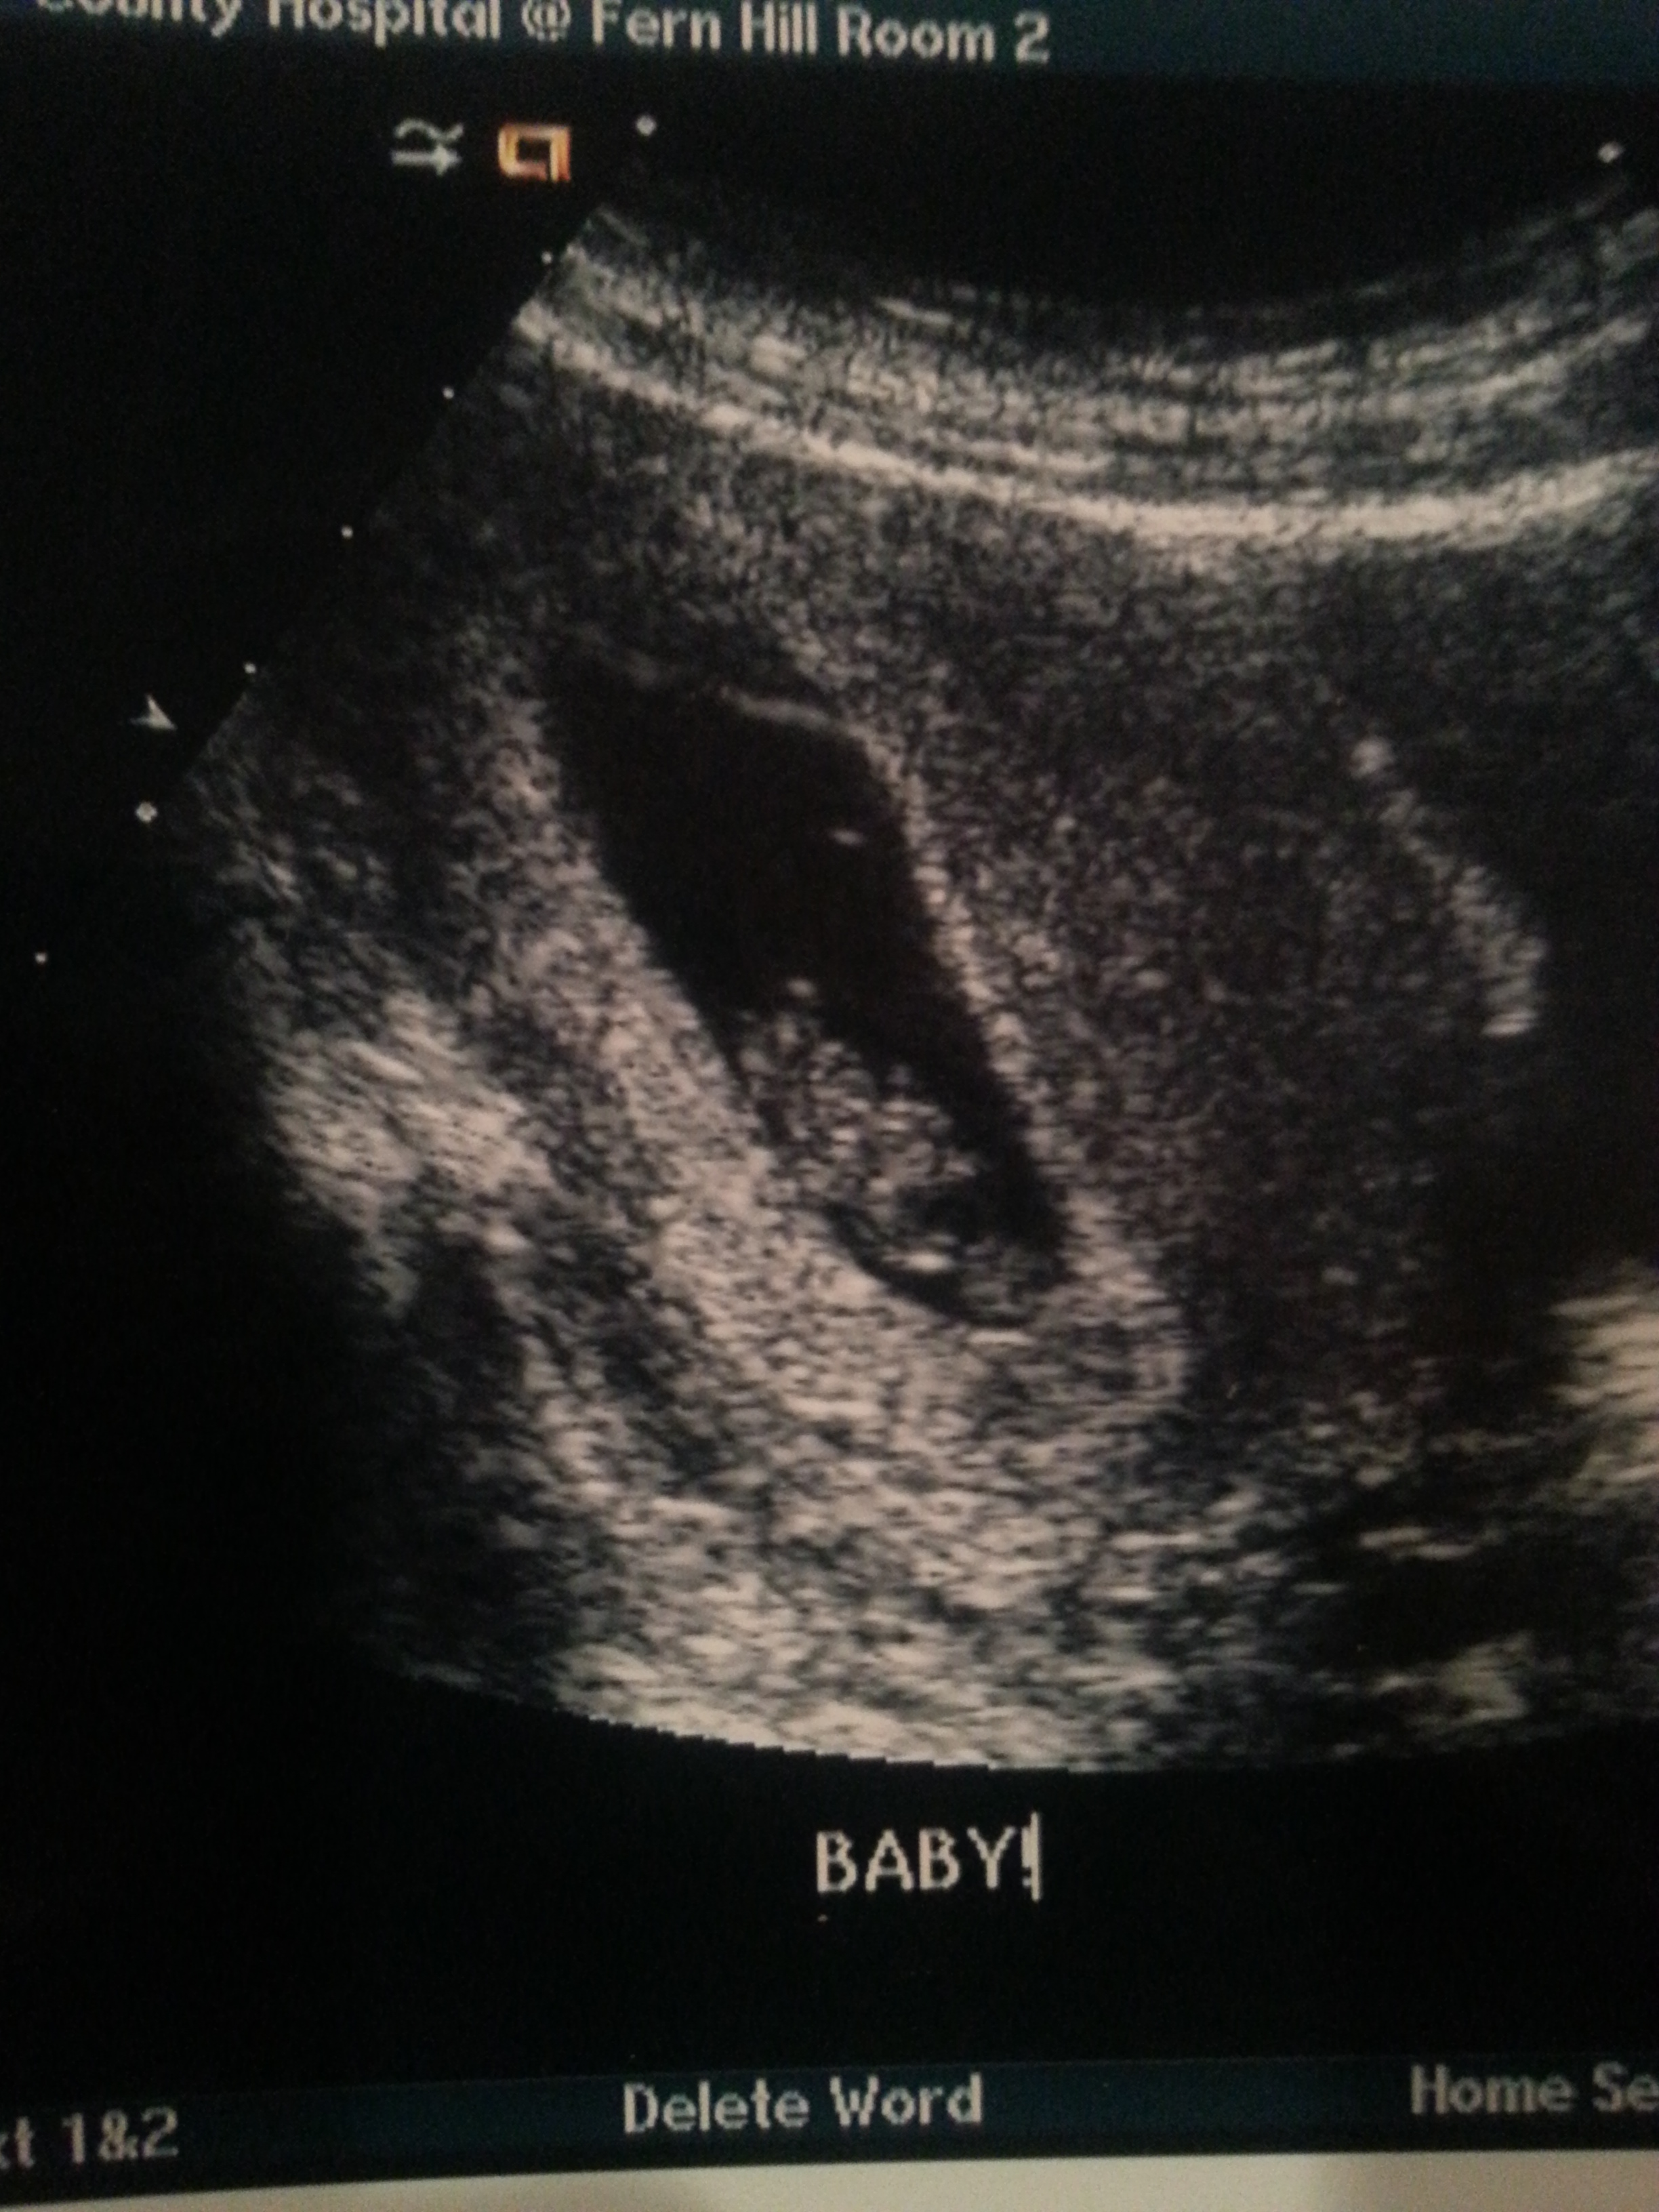

As an added bonus, 2 days ago, i went to have a cyst on my ovary looked at and ended up getting a good long look at my little peanut!!! They decided to go ahead and do a "first trimester" scan which was nice, and so they took all sorts of measurements and had an in depth look at everything. It was actually an ultrasound tech performing it for a change...This was a real treat and not what i'm accustomed to. My doctor usually does quick scans and isn't very thorough.....I had the luxury of being at a radiology center that specializes in all this stuff and has far better equipment than my doctor's office where there is only one machine (And its not a very good one). Anyways they dated my pregnancy, i wasn't even sure exactly how far along i was. I turned out to be 8w4d, according to dates i thought i was one day further but no biggie! I have an EDD of July 16th

I even got to hear the heartbeat for a brief second which was amazing, the heart was beating at a strong 170bpm-She measured it twice and averaged it out to that. Here is the bean, measuring pretty much right on track!! It seems alot more real to me now